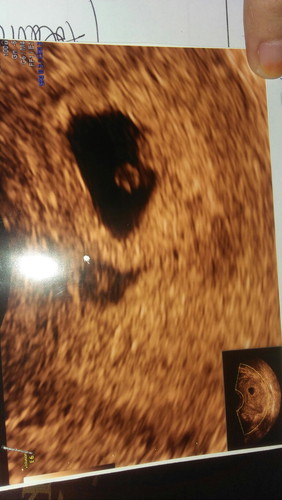

sudah berapa umur kandungan?